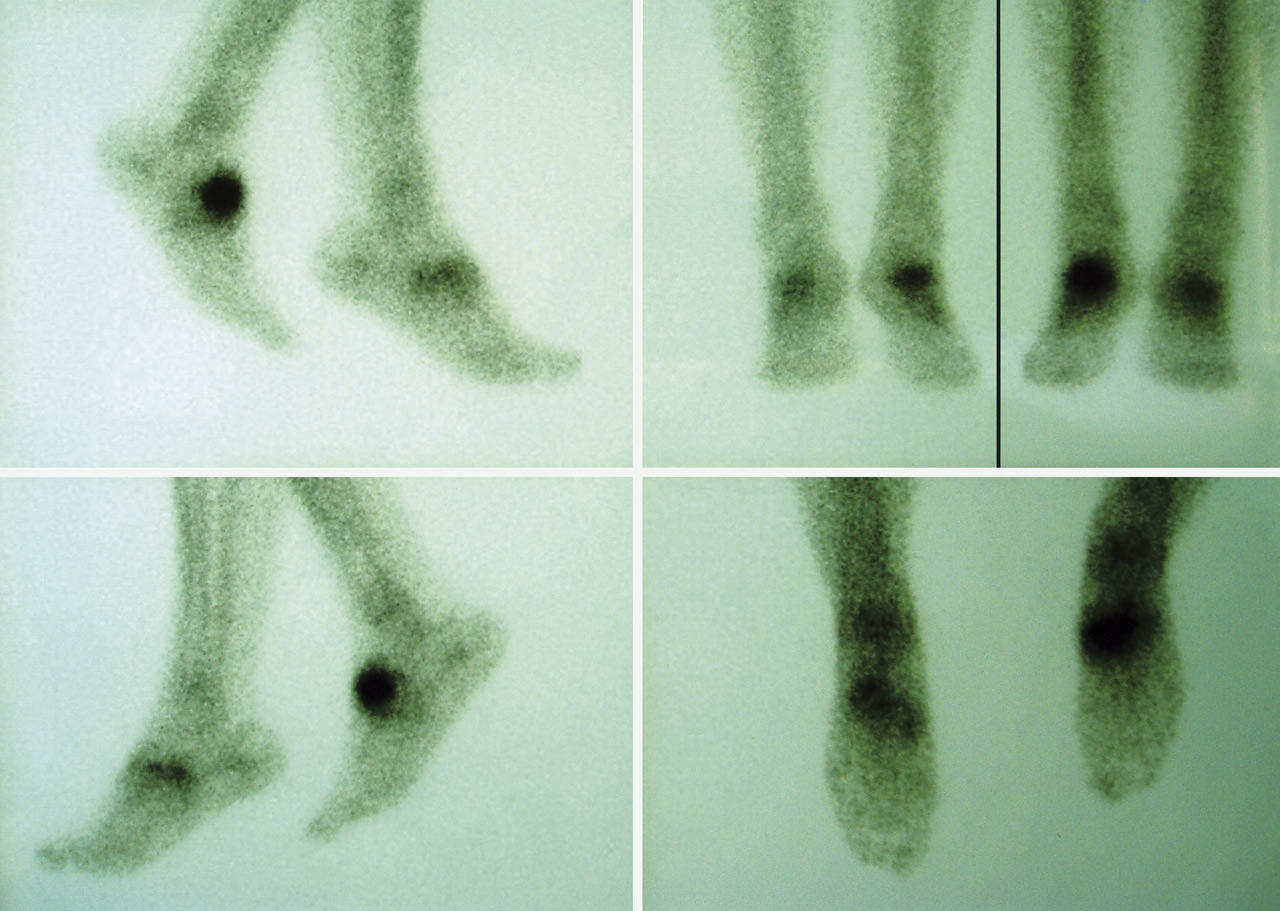

También se hizo un estudio gammagráfico (Figura 4) donde se aprecia un incremento de actividad en la fase vascular, en la fase tisular y en el estudio óseo tardío, lo que indica la presencia de componente inflamatorio añadido a la pseudoartrosis.

Figura 4. Gammagrafía.